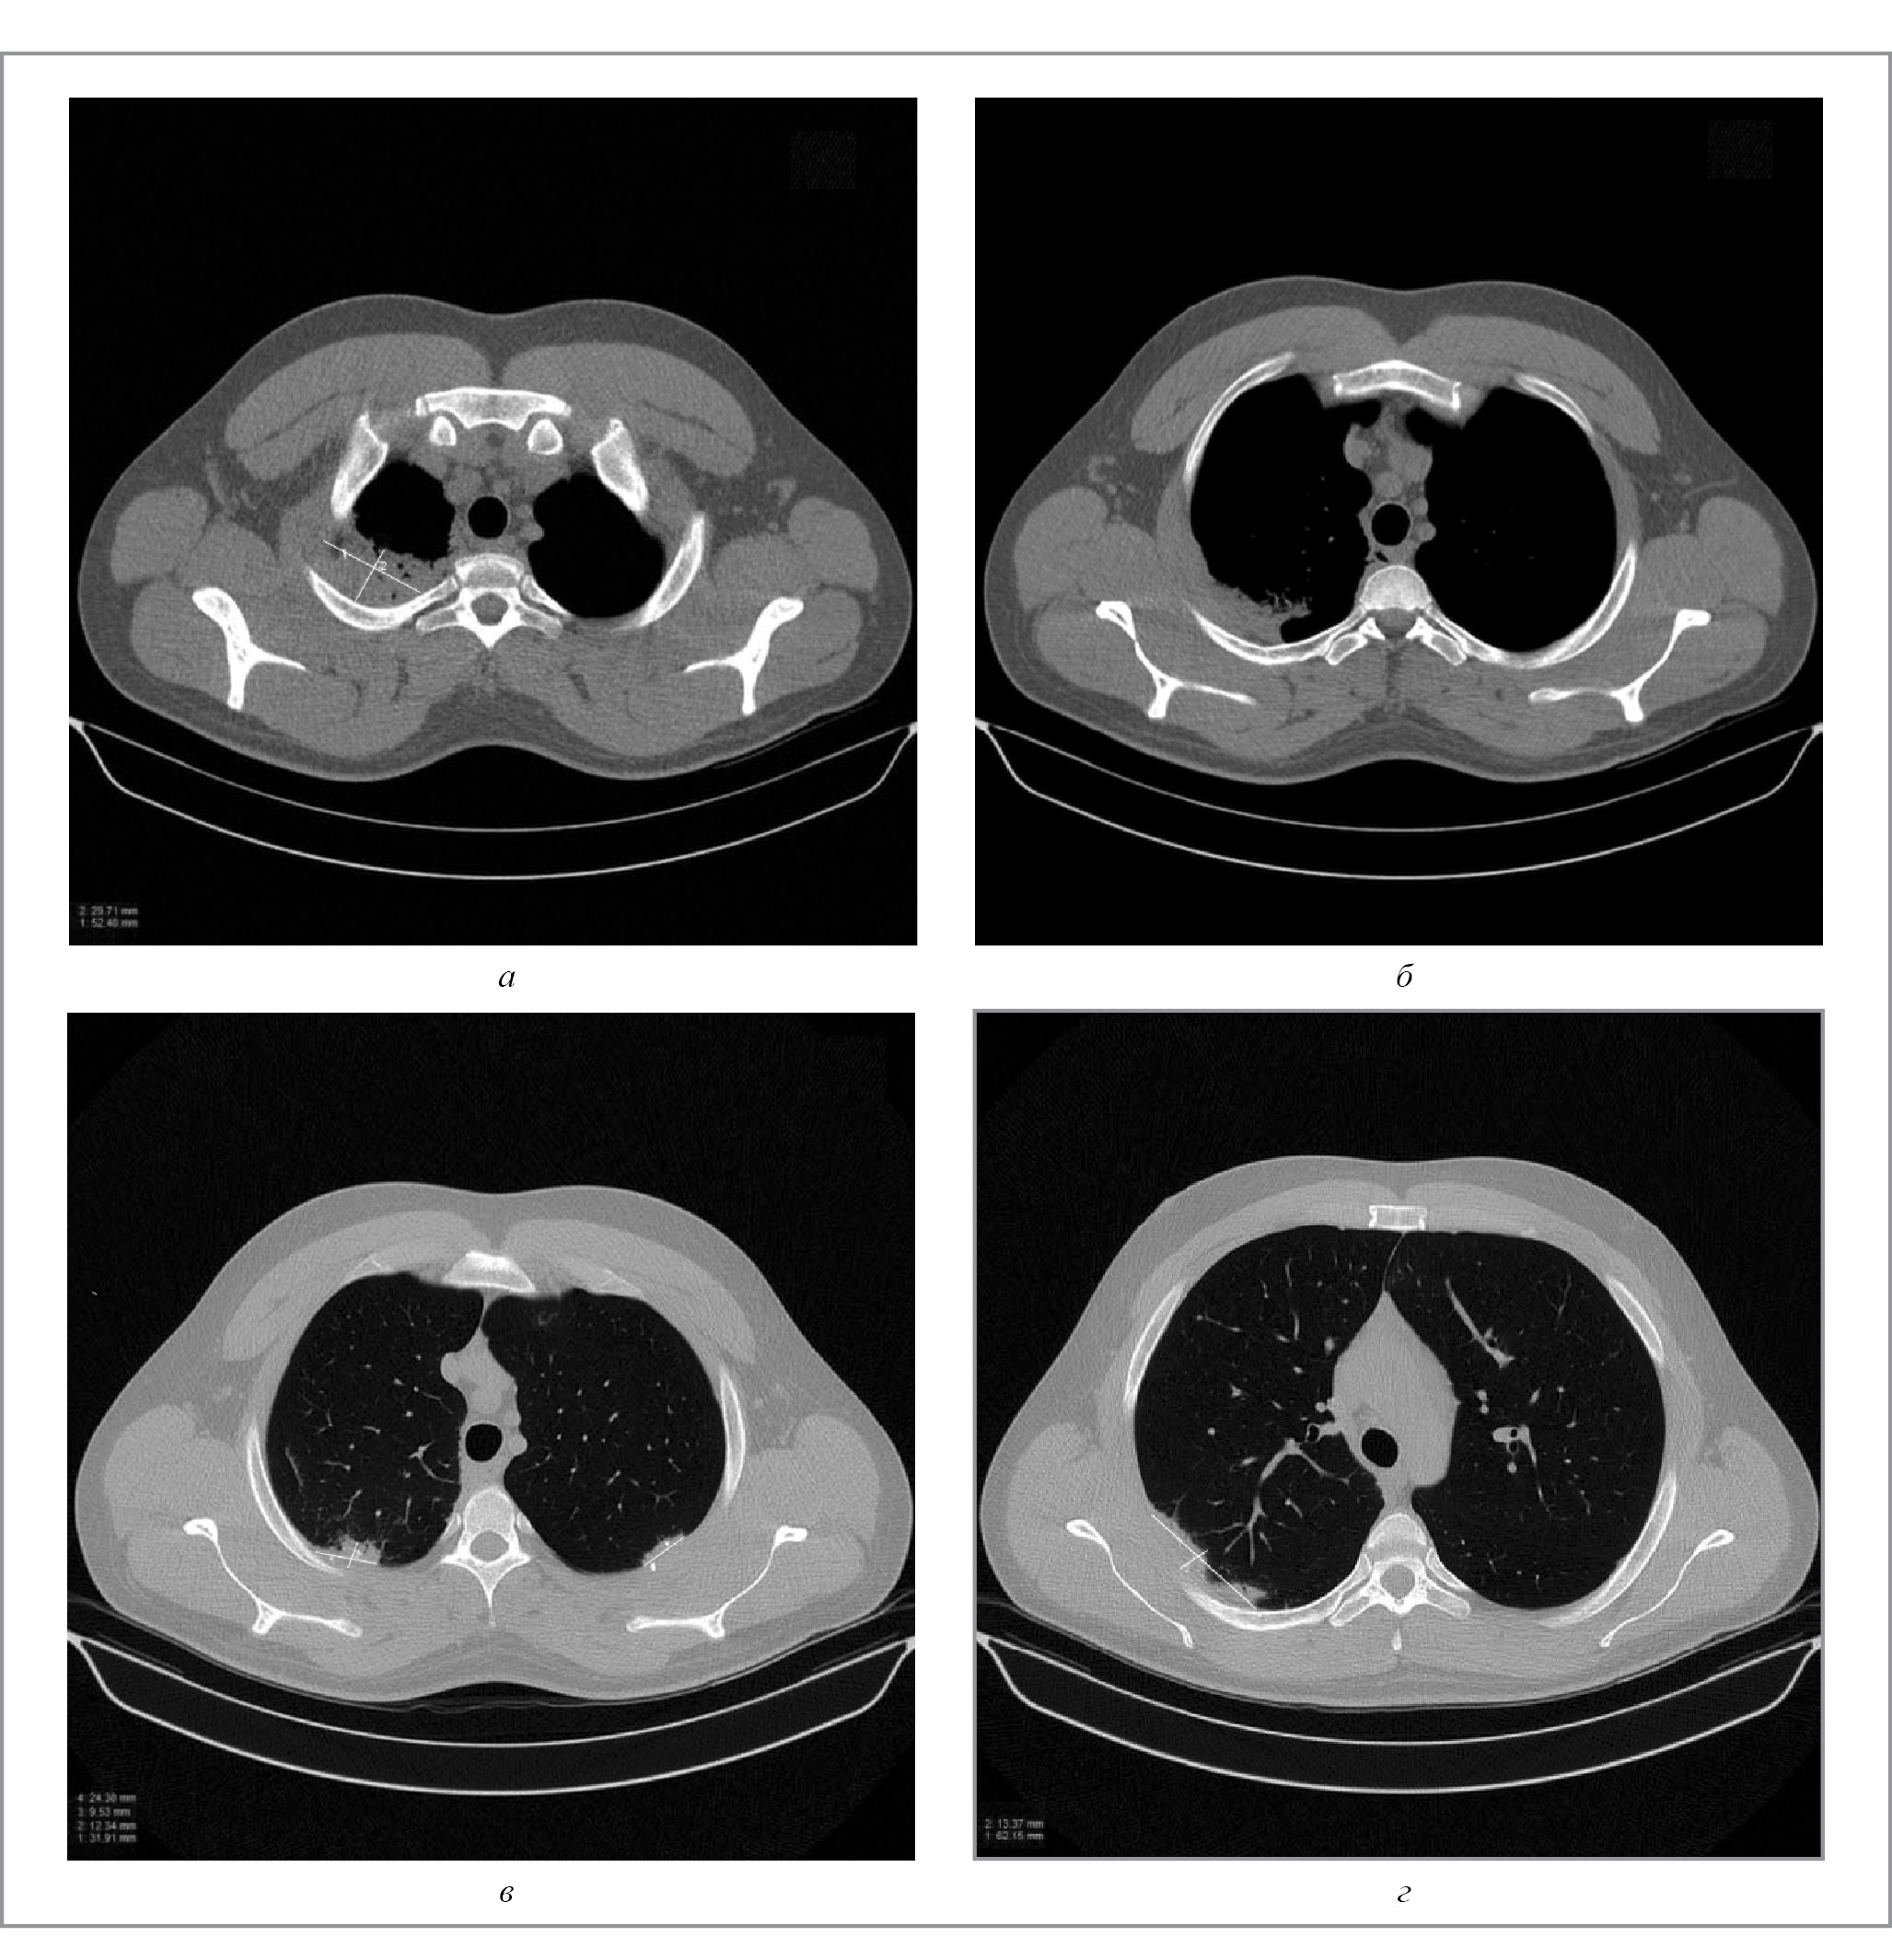

При поступлении у больного отмечались бледность кожных покровов, частота дыхательных движений 18 в минуту, лихорадка до 38ºC, жесткое дыхание при аускультации легких, хрипы не выслушивались. В крови определялись признаки высокой воспалительной активности (СОЭ – 56 мм/ч, С-реактивный белок – 166 мг/л, лейкоцитоз – 13×109/л, фибриноген – 8 г/л, тромбоцитоз – до 850×109/л). Выполнена мультиспиральная компьютерная томография (МСКТ) органов грудной клетки, при которой выявили признаки полисегментарной пневмонии – очаги билатеральной инфильтрации в различных сегментах легких, расположенные преимущественно субплеврально. В S1, S2 c распространением вдоль междолевой плевры и парамедиастинально, в S5, S6, S8, S9, S10 правого легкого и S2, S3, S6, S8, S9 левого легкого определялись зоны консолидации неправильной формы, с широким основанием, обращенные к костальной плевре, видимыми просветами бронхов на их фоне, стенки которых неравномерно утолщены (рис. 1).

Рис. 1. Результаты МСКТ органов грудной клетки пациента С. при поступлении в отделение: а – срез легких (887 мм), с очагом верхней доли размером 29×52 мм; б – срез на уровне 902 мм; в – на уровне 911 мм; г – на уровне 948 мм.